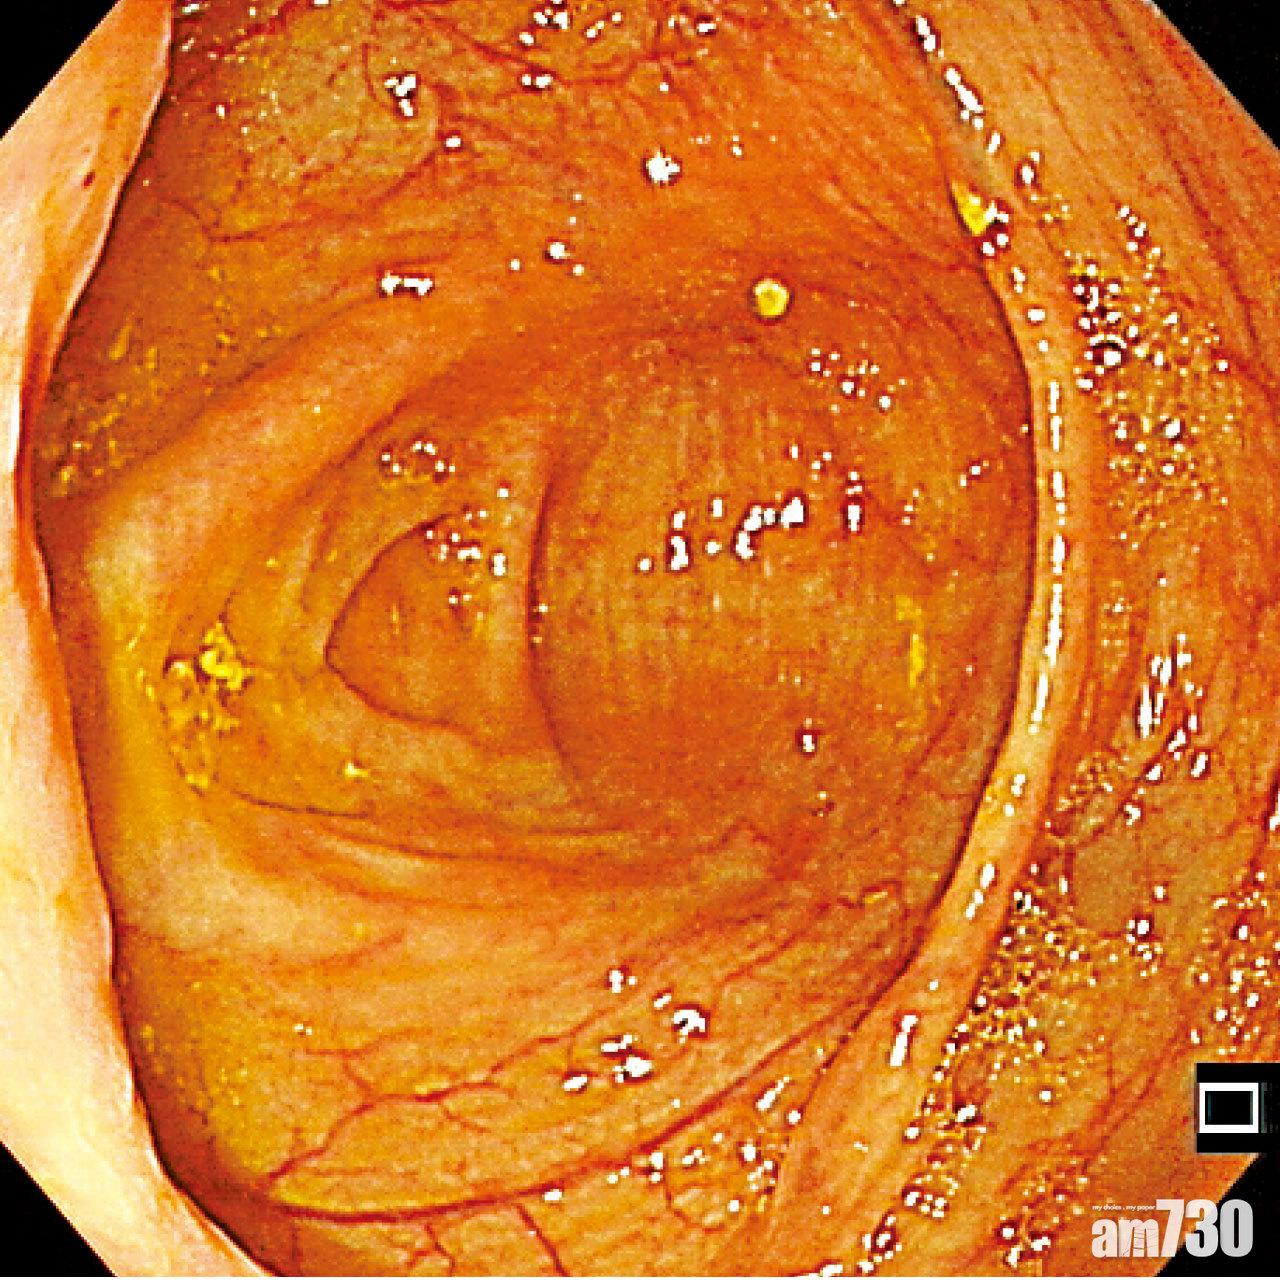

▲健康腸道內壁